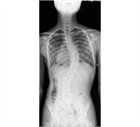

1. 若年者での脊柱変形は、先天性側弯症や思春期に発症する特発性側弯症が多く、通常痛みや機能障害を伴わない場合が多いが、成長に伴い変形が増悪する可能性が高いので見過ごしてはならない。特に特発性側弯症は、思春期の急速な成長期に進行するリスクが高いため、早期発見と適切な介入が重要である。